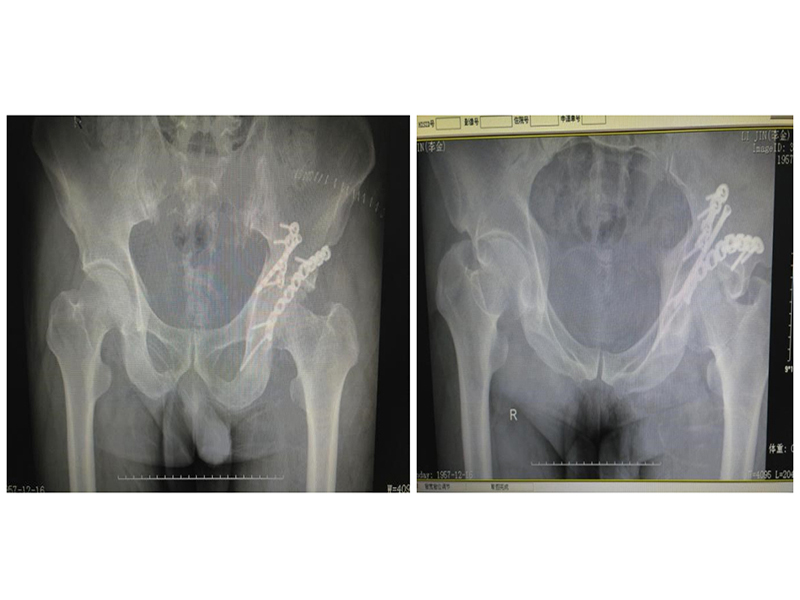

(1).jpg)

• DR